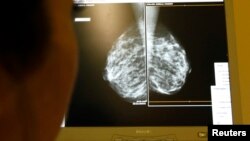

Врачи полагаются на рентгеновское излучение, анализируя снимки на наличие аномалий, которые могут быть маркерами рака груди.

Однако все больше маммологов считают стандартный двухмерный рентген недостаточно эффективным устройством. Доктор Негар Голесоркхи – хирург-маммолог, практикующий в Вирджинии – отмечает, что обнаружение опухоли в тканях груди с помощью стандартной маммографии подобно поиску «черной кошки в темной комнате».

До недавнего времени рентген был лучшим инструментом диагностики рака груди, пока несколько лет назад Администрация по контролю за продуктами питания и медикаментами не одобрила технологию 3D для маммограмм.

Доктор Сара Фридвальдт, практикующая в иллинойском госпитале в Парк Ридж рассказала «Голосу Америки», что ее команда завершила исследование с участием 450 тысяч женщин – используя технологии 2D и 3D.

Доктор Фридвальдт выявила, что разница между аппаратами – огромная. Опухоли, которые трудно увидеть на стандартной маммограме было легко обнаружить на 3D снимках.

По ее словам, «мы обнаружили опухоли...те самые, которые могут стать потенциальными убийцами – чаще в 3D, чем на 2D маммограммах».

3D маммограммы позволили снизить число ошибочных диагнозов, поэтому меньше женщин были вынуждены продолжать болезненные тестирования и ненужные биопсии, добавила она.

По меньшей мере, одно из новых исследований выявило почти аналогичные результаты – 3-D снимки позволили обнаружить почти на 30 процентов больше опухолей, чем стандартные маммограммы. Новая технология повысила вероятность обнаружения злокачественных опухолей на 40 процентов.

Трехмерные маммограммы настолько эффективнее стандартного рентгена, отмечает доктор Фридвальдт, что медицинское сообщество рассчитывает, что в ближайшем будущем 3D полностью заменит технологию 2D в диагностике рака груди.